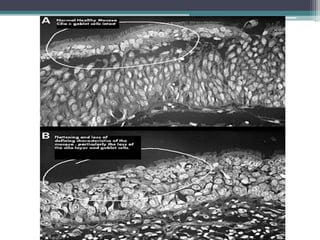

• Microscopic changes

NORMAL

squamous metaplasia

Absence of cilia

Atrophy of

muscosal glands

Atrophy of nerve endings and

olfactory nerve